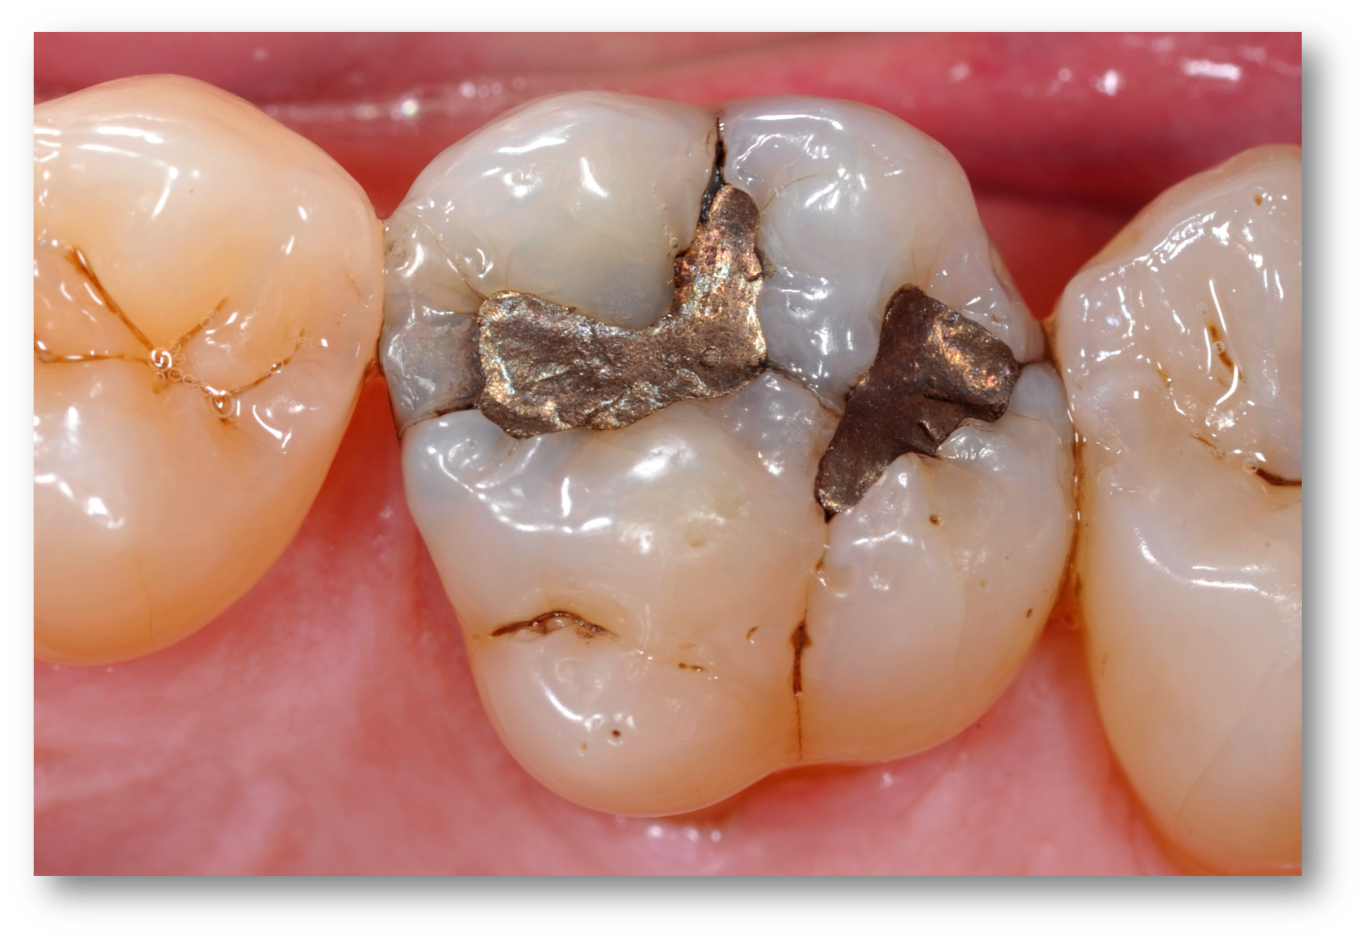

Example 5: Cracked-Tooth Syndrome

A patient with an example of cracked-tooth syndrome, seen in Figure 8, presented with thermal sensitivity, pain to bite, no periapical radiolucency, and no spontaneous pain. In general, the dentist should drill until there is no leakage around the crack: no ring or stain around the crack inside the dentin, no separation of the pieces, and no decay (Figure 9). Caries indicators may be used to guide by highlighting elements such as horizontal and vertical cracks in teeth that may otherwise go unnoticed. The preparation and procedural steps were essentially the same as in the previous examples: etching, rinsing, bonding, a layer of Giomer flow, light-curing, and then remaining materials were placed. All the materials were radiopaque and thus could easily be seen on a radiograph (Figure 10).

Fig 8. Cracked-tooth syndrome.

Figure 8

Fig 9. The clinician should drill until there is no leakage around the crack.

Figure 9